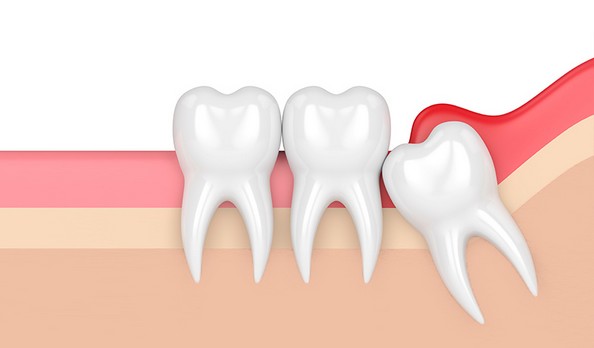

Extractions

Consulter son chirurgien Dentiste, Je suis contre les extractions, sauf en cas de force majeure.

Ma vocation est de sauver vos dents